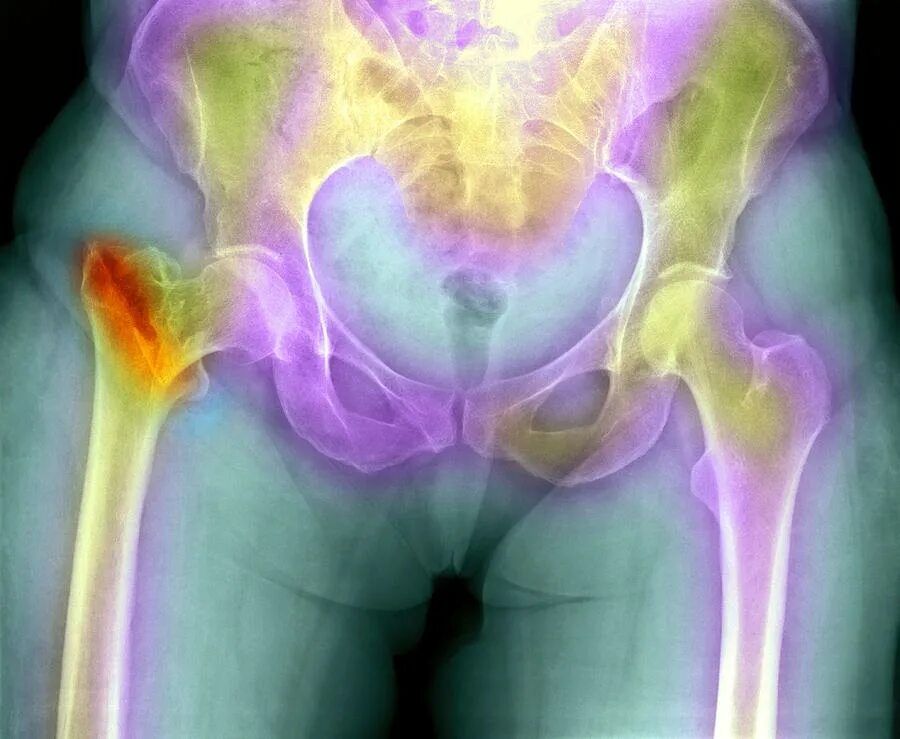

Воспаления сухожилий тазобедренного